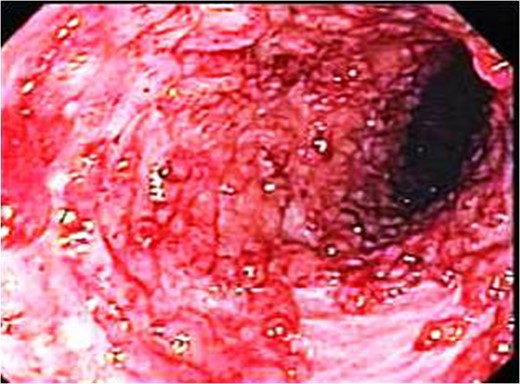

Endoscopic picture showing markedly elevated erythmatous mucosal surface with bleeding and erosions.